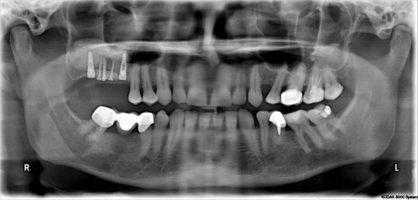

Синус-лифтинг, наличие костной перегородки. Зафиксированный нижнечелюстной костный блок и установленные имплантаты. Рана ушита пародонтологическими и узловыми швами

Ортопантомограмма после операции

Ортопантомограмма пациента А. после операции

Ортопантомограмма пациента А. после дентальной имплантации

Ортопонтомограмма пациента Б. пациента до операции

Ортопантомограмма после операции и зафиксированный костный трансплантат

Ортопантомограмма пациента Б. после операции

Ортопантомограмма пациента В. до операции